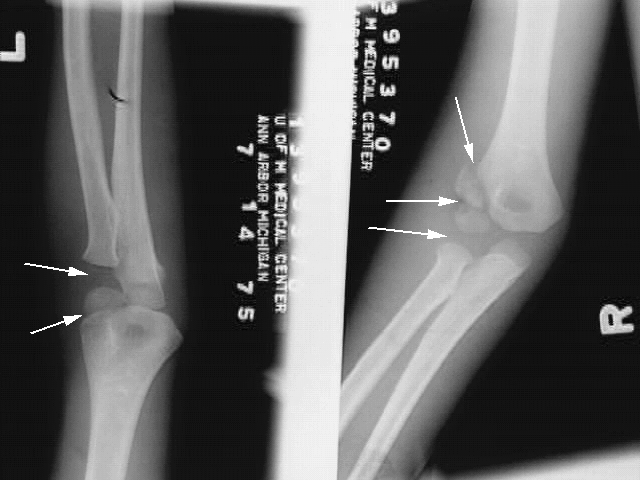

Upper Limbs: Elbow Dislocation:

1. Left: Arrows: Fractured Head of the Radius

2. Right Arrows: Fractured Capitellum and Lateral Epicondyle.